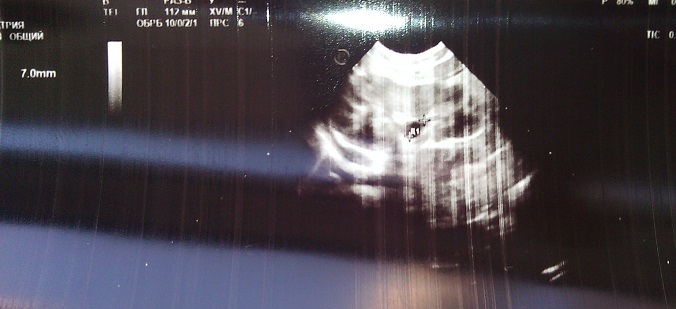

Заболевания мочеполовой сферыСходили мы сегодня на узи, нам 1,5 месяца и нашли пиелоэктазию лоханки 7 мм слева. Во время беременности почки были у сына нормальные. узи делали каждые 2 недели в роддоме, не пропустили бы.

Врач сказали типа норма, у кого было, что делали и пройдет ли?